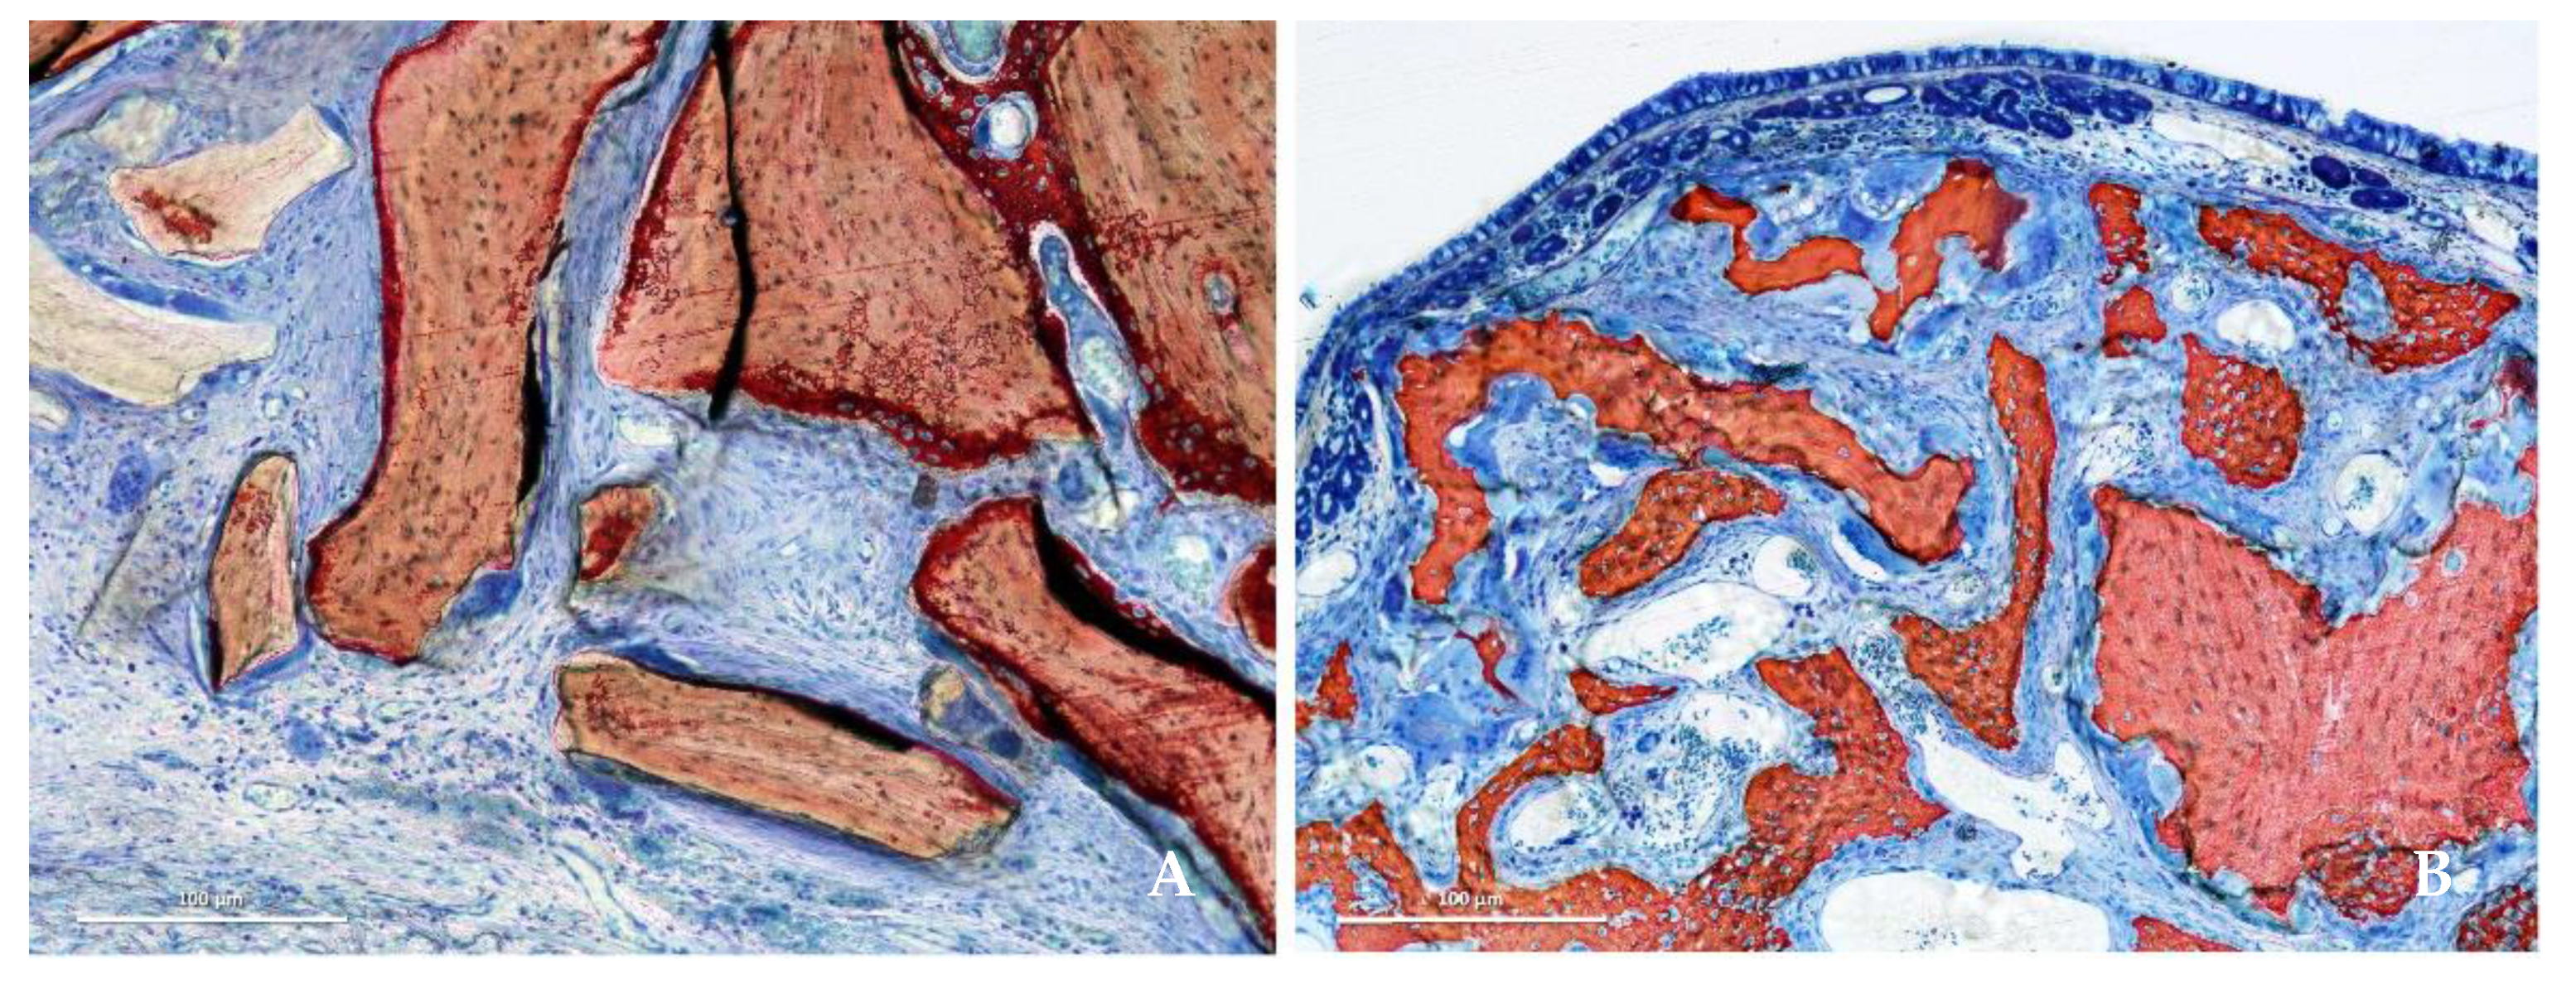

3. Results